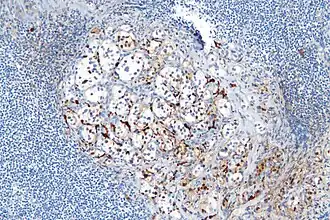

- Cerca de 40% dos tumores carcinoides apresentam dispersões de células sustentaculares, que se coram positivamente para S-100.[6]